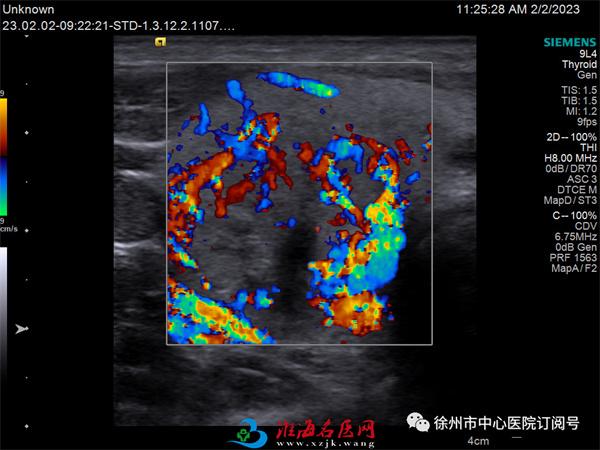

术前甲状腺肿瘤血流丰富,

提示有活性

微波消融术后瘤体内血流信号消失,提示没有活性